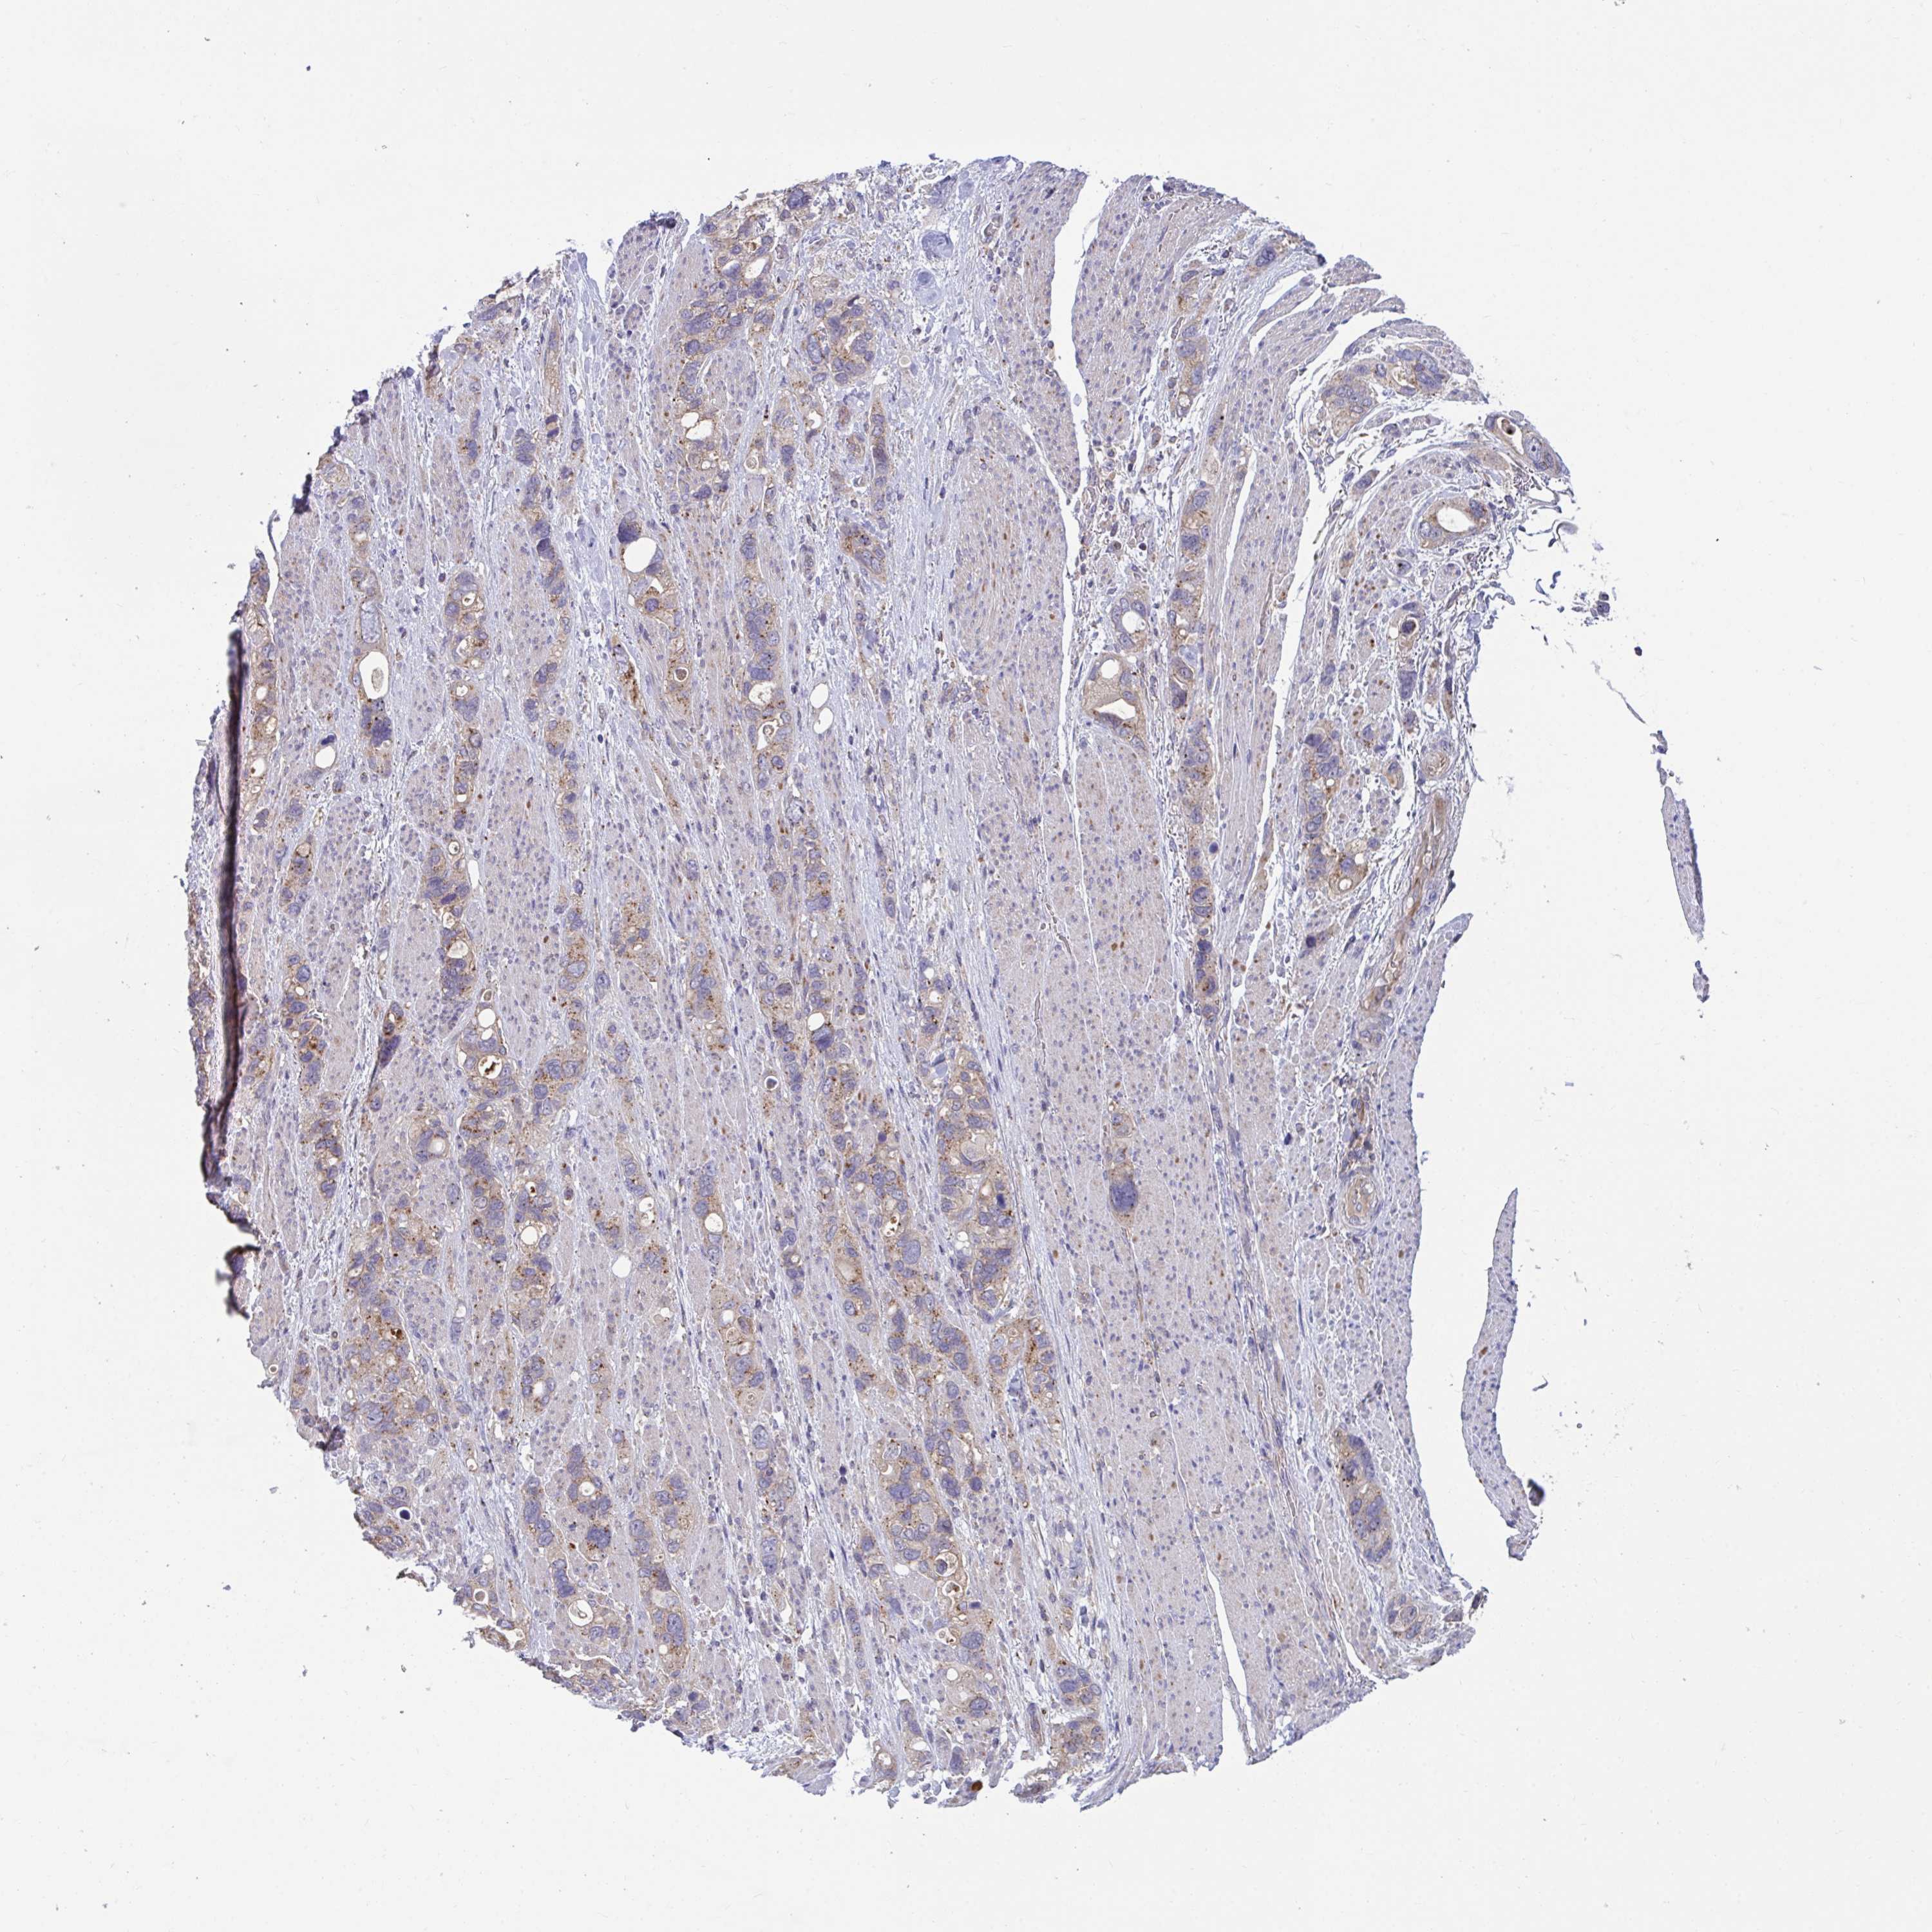

STOMACH CANCER - Protein expressioni

A mouse-over function shows sample information and annotation data. Click on an image to view it in a full screen mode. Samples can be filtered based on level of antibody staining by selecting one or several of the following categories: high, medium, low and not detected. The assay and annotation is described here.

Note that samples used for immunohistochemistry by the Human Protein Atlas do not correspond to samples in the TCGA dataset.

Antibody stainingi

Antibody staining in the annotated cell types in the current human tissue is reported as not detected, low, medium, or high, based on conventional immunohistochemistry profiling in selected tissues. This score is based on the combination of the staining intensity and fraction of stained cells.

Each image is clickable and will lead to virtual microscopy that enables deeper exploration of all samples and also displays staining intensity scores, fraction scores and subcellular localization as well as patient and tissue information for each sample.

Antibody HPA041802

Antibody HPA054532

Staining

High

Medium

Low

Not detected

Intensity

Strong

Moderate

Weak

Negative

Quantity

>75%

75%-25%

<25%

None

Location

Nuclear

Cytoplasmic/membranous

Cytoplasmic/membranous,nuclear

Adenocarcinoma, NOS

Adenocarcinoma, High grade